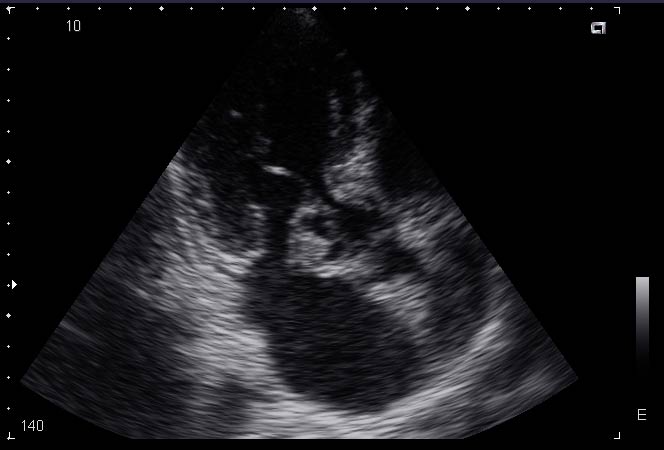

ПРИ ПЛАНОВОМ ОБСЛЕДОВАНИИ ПОСЛЕ ПЕРЕНЕСЕННОГО МЕЛКООЧАГОВОГО ИНФАРКТА МИОКАРДА ПОЛУЧИЛАСЬ ТАКАЯ КАРТИНКА. КАК ДУМАЕТЕ, ЧТО ЭТО МОЖЕТ БЫТЬ. И ТАКТИКА.

КЛИНИЧЕСКАЯ КАРТИНА СЛЕДУЮЩАЯ: ЛИХОРАДКА В ТЕЧЕНИЕ 4Х МЕСЯЦЕВ, ЛЕЧИЛАСЬ В ИНФЕКЦИОННОЙ БОЛЬНИЦЕ С ДИАГНОЗОМ ЛИХОРАДКА НЕЯСНОГО ГЕНЕЗА, АНЕМИЯ СРЕДНЕЙ СТЕПЕНИ, АСТЕНИЗАЦИЯ.

Наиболее вероятен бактериальный септический эндокардит с поражением ПС МК, абсцесс створки?

дело в том, что клапан как-бы и не изменён, может не очень хорошо видно на картинках и ролике, а это образование крепится у основания створки. Просто ни с чем подобным раньше сталкиваться не приходилось, да и в литературе подобных картинок нет. Как вариант, абсцесс тоже рассматривается. Диагноза точного пока нет. Вероятно больную направят в РНПЦ Кардиологии, результат обязательно сообщу.

Следует дифференцировать инфекционный эндокардит и опухоль сердца.

Для инфекционного эндокардита сроком давности 4 мес хотелось бы иметь большую степень поражения митрального клапана в виде его недостаточности (митральная регургитация, дилатация и объемная перегрузка левых отделов сердца).

Для опухоли, которая чаще всего представлена миксомой, не совсем типично место, из которого она исходит.

А клиника может быть сходной. Описан синдом отравления опухолью даже для миксом.

Больше данных в пользу инфекционного эндокардита с абсцессом передней створки митрального клапана. Учитывая анамнез можно предположить, что больной проводилась антибиотикотерапия, поэтому процесс на створке не привел к выраженной митральной недостаточности. В данном случае, мне кажется, необходим динамический ЭхоКГ-контроль на фоне лечения антибиотиками (с учетом диагноза ИЭ).